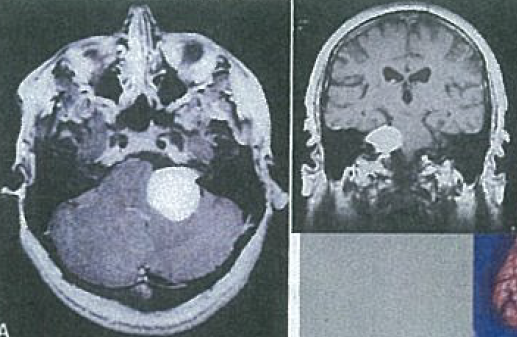

If you see these in a child, what are they and what do you look for further?

These are multiple meningiomas, look for NF2

45 year old woman

Cerebellopontine angle tumor, most likely a Schwannoma aka Neurilemoma